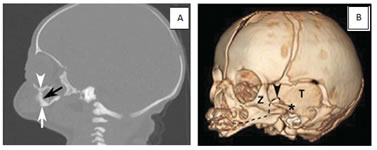

Figure 2: A, Sonogram of a fetus with maxillomandibular fusion showing lack of a normal gap between the mandible (arrow) and maxilla (arrowheads). Also note the small chin and protuberant lips in comparison with B and C. B and C, Sonograms of unaffected fetuses of the same gestational age with closed mouths. Note the substantial gap between the mandible (arrows) and maxilla (arrowheads) in both cases compared with A. Figure 3: The fetal MRI showing a small chin, a characteristically protruding jaw, and prominent, protruding lips Figure 4: Postnatal CT of the affected neonate. A, Postnatal off midline sagittal head CT showing fusion (black arrow) of the mandible (white arrow) and maxilla (arrowhead). Fusion was seen on multiple slices, more easily visualized on the 3D CT reconstruction (B). B, Postnatal 3D CT reconstruction of facial bones. Sagittal view depicts fusion of the maxilla and the mandible. The fusion in this case involved bilateral bony fusion of the mandibular and maxillary alveolar processes, with a small anterior slit remaining. The fusion also included fusion of the proximal parts of the mandibles, the ascending rami, to the posterior portions of the maxillas and to the zygomas bilaterally. However, the ascending rami of the mandibles were not fused to the zygomatic processes (asterisk) on either side. The coronoid processes of the mandible (arrowhead) are visualized, pointing to the most proximal aspect of the mandible. T indicates temporal bone; and Z, zygomatic bone. The dotted line represents the expected area of separation between the mandible and the maxilla. DISCUSSION Maxillomandibular fusion has always been an unanticipated diagnosis made at birth. Given that congenital oral cavity deformities have potential for causing difficult airway and respiratory impairment, prenatal diagnosis would allow appropriate preparation of staff for airway management at the time of delivery. Given the advanced imaging techniques available today, such as real-time sonography and fast sequences for fetal MRI, maxillomandibular fusion can potentially be detected prenatally.6 The reported sonographic findings in a case of maxillomandibular fusion, were an absence of mouth opening and a contiguous appearance of the upper and lower jaws. In normal fetus, there is normally a gap between the maxilla and mandible on sonography. Various studies have reported real-time sonography as a reliable method for the evaluation of fetal movement, particularly fetal facial expressions, in the second and third trimesters.8 These studies reported mouth opening in the context of swallowing, suckling, chewing, and even yawning detected by real-time sonography in fetuses without abnormalities. According to these studies, continued observation by real-time sonography (for anywhere between 15 minutes and 2 hours, depending on the study) is a reliable and reproducible method for visualizing fetal mouth opening. One of the studies even reported regular mouth openings during fetal quiet and active sleep states.9 Because fetuses with maxillomandibular fusion are incapable of opening their mouths, real-time sonography can a definite method of excluding this rare disorder in suspected cases. Real-time sonography would be best performed during the second trimester for optimal visualization of the fetus. 3D and 4-dimensional (4D) sonography can also be valuable in suggesting or diagnosing maxillomandibular fusion prenatally. Numerous recently published articles emphasized that the interpretation of the fetal image, especially of the fetal face, is easier and faster with 3D images than with 2-dimensional (2D) images.10,11 Three dimensional sonography has the capability of showing planes of a section that cannot be obtained with 2D sonography and thus allows for a comprehensive evaluation of facial anatomy. Kurjak et al11 commented on the specific advantages of the assessment of the maxilla and mandible for the diagnosis of micrognathia and retrognathia. Surface-mode rendering, in which the surface within the volume of interest (generally the skin) can be seen without the underlying tissue, has proven very useful in the evaluation of facial abnormalities.10 In the case presented here, the facial characteristics visualized on the The fetal MRI shows the maxillary and mandibular tooth buds to be closely apposed without the intervening space seen in unaffected fetuses. MRI revealed an open mouth on most sequences in all fetuses without maxillomandibular fusion.5,6 MRI would likely have been identified on 3D sonography if performed during the second trimester. The maximum-rendering mode highlights the maximal echo (bone) information of a volume data set and is an ideal tool for the 3D reconstruction of bony structures. Generally, cranial bones, the ribs, and other curvilinear bones, which cannot be properly visualized in a single 2D plane, are better assessed in a maximum- mode projection.11 Selectively imaging the bones on sonography can undoubtedly add to the potential of sonography for suggesting or diagnosing bony maxillomandibular fusion. Finally, 4D sonography, by adding the temporal component (as a virtually live 3D image) in the surface-rendered mode, has been described as advantageous in accurate visualization of subtle and fast facial expressions.11 The use of 4D sonography to monitor small or fast jaw and mouth movements (complementary to real-time conventional 2D sonography) would also be of potential value in the evaluation of suspected cases of maxillomandibular fusion. Both the management and outcome of patients with bony maxillomandibular fusion have varied. The rarity of the condition makes standardization of treatment difficult.